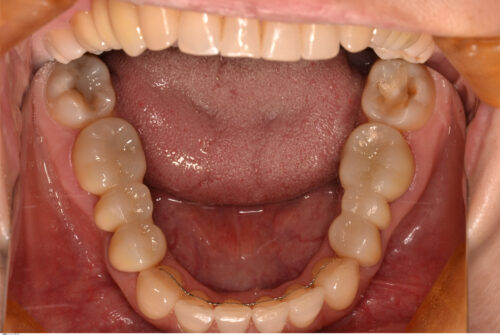

開始から1年で治療を終えました。矯正治療開始直後から、食いしばれなくなるせいか頭痛の改善も認められ、現在も良好に経過しています。

現在術後3年が経過し、後戻りも無くリテーナーの使用も終了しています。

本来であれば欠損部分も矯正によってスペースを無くせばブリッジを入れる必要がなくなるのですが、下顎は骨が硬いため移動に時間がかかります。治療期間を短くすることで患者さんの負担も減るので、成人矯正の場合は補綴処置を組み合わせながら治療計画を立てることも重要だと思います。